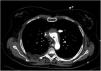

Paciente que ingresa en el hospital por síndrome coronario agudo complicado con comunicación interventricular (CIV). En un inicio se realiza tratamiento con angioplastia primaria y corrección quirúrgica de CIV. Durante el procedimiento desarrolló shock cardiogénico, con necesidad de balón de contrapulsación intraaórtico y ECMO-VA. A pesar del tratamiento hubo persistencia de CIV, por lo que se propone para trasplante cardiaco en centro de referencia. Previo a ello, se realiza angioTC con imagen compatible con disección de aorta ascendente (figs. 1 y 2), por lo que se desestima. Tras la revisión de imágenes en el centro trasplantador, se descarta disección tras valoración en ecocardiografía transesofágica del arco aórtico (fig. 3), considerando que la imagen se produce por confluencia de flujos de ECMO, lo que permite el trasplante.